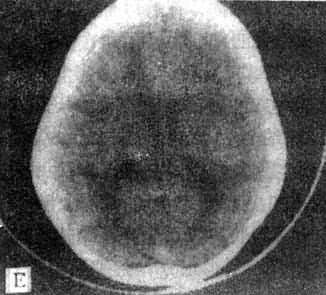

10mm底颅层面 此层面通过眦耳线上方10mm,由前向后可见眼眶上部、蝶窦和中颅凹底、枕骨及枕大孔等颅底结核。20mm蝶鞍层面 可见垂体、四脑室、桥池和桥小脑角池、岩锥与内耳道、前、中和后颅凹脑组织结构。本层面重点观察垂体和后颅凹结构。(图5-1-4A)。30mm鞍上池层面 可见鞍上池呈六角星或五角星形低密度脑脊液间隙,增强CT扫描尚可见脑底动脉环在池内的分布情形(图5-1-4B)。鞍上池后方、环池和四叠体池包绕部分即为中脑。40mm三脑室前部层面 重点观察内囊、基底节和丘脑区(图5-1-4C)。50mm三脑室后部层面除显示内囊、基底节和丘脑区外,同时是观察三脑室后部松果体区重点扫描层面(图5-1-4D)。60mm侧脑室体层面可观察侧脑室体部、三角区和后角(图5-1-4E);增强CT尚可见直窦、上矢状窦和大脑镰强化显影。70mm侧脑室顶层面 可见侧脑室顶部、大脑纵裂、脑皮质和脑髓质(图5-1-4F)。80~100mm脑室上层面 脑皮、髓质、脑沟和大脑纵裂清楚显示。

图5-1-4 正常头部CT扫描

E、侧脑室体部层面 F、侧脑室顶层面